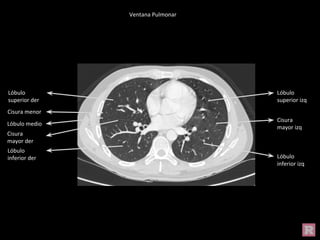

Ventana Pulmonar

Lóbulo superior

izq

Lóbulo superior der

Lóbulo inferior izq

Lóbulo superior der Lóbulo superior

Cisura mayor izq

Lóbulo inferior der

Cisura Mayor der